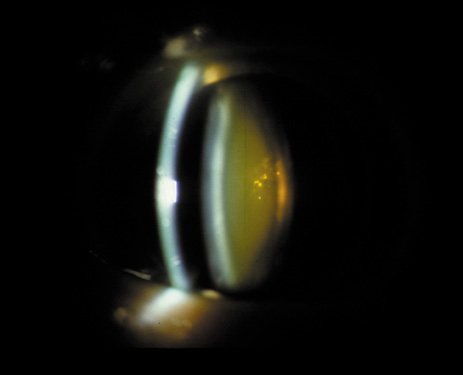

CORTICAL CATARACTS

The cortical cataract is often the most common subtype of opacity seen in African-derived populations.18 The cortical layer is approximately 2 mm thick anterior and posterior to the nucleus in adults, and its metabolically active new cortical fibers are continuously laid down by the bow region cells. The cortical layer is less compact than the nucleus and is therefore more prone to becoming overhydrated as the result of an electrolyte imbalance. This may eventually lead to disruption of the lens cortical fibers, as demonstrated in diabetes25 (Fig. 7) and galactosemia.26 It has therefore been proposed that this type of cataract may be partly caused by osmotic stress. Early changes may include signs such as vacuoles, water clefts, and lamellar separation (Fig. 8). These changes may come and go over time, but eventually they may lead to damage and irreversible opacification of some fibers. Recent studies have also suggested that an abnormality of the maturation process of the lens fibers may lead to subsequent poor development of the primary, secondary, and tertiary sutures, resulting in the formation of cortical cataracts.27

Fig. 8. Early cortical changes. Vacuoles, water clefts, and lamellar separation.

Cortical opacities have been clinically observed to develop earliest in the inferior half of the lens, especially the lower nasal quadrant.28 Epidemiologic29 and laboratory studies30 have suggested that cortical cataracts may be caused by ultraviolet rays from sunlight. The supraorbital margins may block the ultraviolet rays from falling over the upper part of the lens, thus making cortical cataract less frequent in the upper quadrants. Eventually these opacities also develop in the periphery in other quadrants, resulting in a circular array of spokes and peripheral cuneiform opacities (Fig. 9). Bands of central cortical fibers may become prominent and opacify centrally (Fig. 10). However, most cortical cataracts remain in the periphery for many years, even decades, before the central axis of the lens becomes involved, causing loss of vision late in the development of the cataract.

Fig. 9. Moderate cortical changes. Wedge-shaped (cuneiform) or spoke-like (wheel) peripheral changes are seen. These changes may be extensive but may not affect Snellen visual acuity since they occur in the periphery.

Fig. 10. Central cortical opacities. This type of cortical opacity may causes early diplopia and glare disability.

It has been observed that some individuals may have cortical opacities covering the entire anterior cortical and posterior cortical area (Fig. 11), and yet have 20/40 or better Snellen visual acuity under standard testing conditions. However, these patients may have severe disability glare such that under simulated bright lights their visual acuity may decrease to 20/80 or worse.31 They may also have decreased contrast sensitivity. These individuals tend to do well indoors but have difficulty driving during bright, sunny days, and at night because of oncoming headlights. Treatment in these cases must be decided on an individual basis, and surgery may be indicated when the expected benefits outweigh the surgical risks.

Fig. 11. Advanced cortical cataract. Although this type of cataract may be compatible with a Snellen visual acuity of 20/40 or better, it may give rise to severe glare disability.

This type of cataract is best seen with retroillumination, which gives an enhanced picture of the cortical spokes and vacuoles by the shadows they cast as the light is reflected back by the fundus. Direct illumination helps clarify the level of the opacities (see discussion in the Posterior Subcapsular Cataract section below).